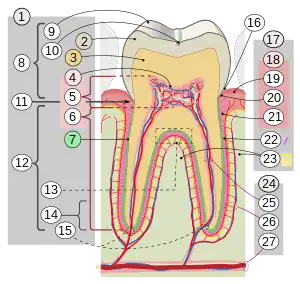

Détail d'une molaire humaine :

|

cementum = cément

en=émail

d=dentine

od=odontoblates

p=papille dentaire